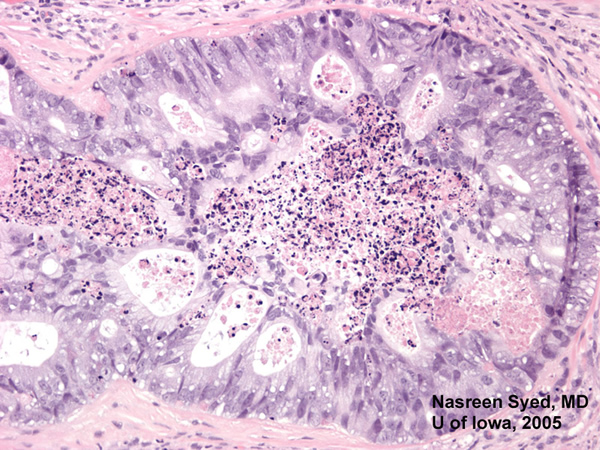

Figure 6: 100x view of glandular tumor with central necrosis. Metastatic adenocarcinoma of the lung